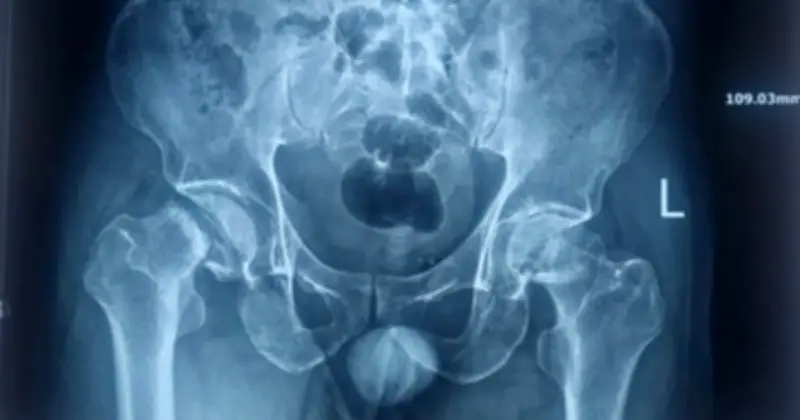

Hình ảnh X-quang trước phẫu thuật cho thấy mức độ tổn thương nặng nề ở cả hai bên chỏm xương đùi, trong khi hình ảnh sau phẫu thuật đã ghi nhận sự thay thế thành công bằng khớp háng nhân tạo, mở ra cơ hội phục hồi chức năng vận động cho bệnh nhân.